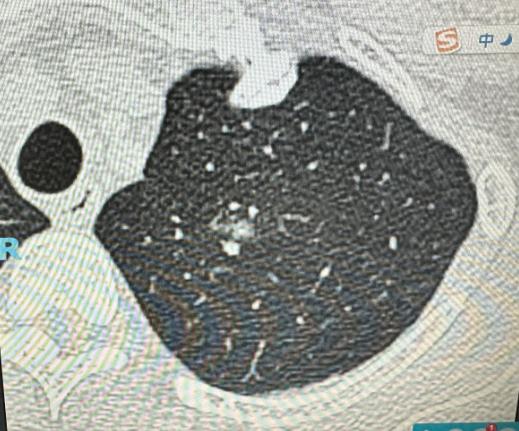

肺结节那么多,哪种最危险?这2种情况一定要警惕!现在很多人体检,一查肺部就会发现有结节,难免会慌神,不知道自己这个结节要不要紧、危不危险。 其实肺结节不是都有风险,大部分都是良性的,但有两种情况,大家一定要提高警惕,别不当回事。 1、看结节的大小,这是判断风险最直接的一个标准 很多人可能不知道,结节的好坏,和它的大小关系特别大。就拿临床上的常见情况来说,只要是5毫米以下的肺结节,不管它是什么类型,基本上都不会对身体健康和生命安全造成威胁,大家完全不用过度焦虑,定期复查就行。 但如果结节的大小超过了1厘米,风险就会慢慢升高,尤其是结节长到2厘米、3厘米的时候,恶性的概率会明显增加。所以大家体检时,要是查出结节比较大,千万不能掉以轻心,一定要放在心上,及时咨询医生。 2、肺结节在观察期间发生了变化 对于那些小于1厘米的小结节,大部分情况下都没有危险,临床上一般都会建议定期复查,重点就是看它有没有变化。 如果在复查的时候,发现这个小结节和之前比不一样了——比如变大了、形状变不规则了,或者密度变高了,这种情况就必须特别重视,得进一步检查,弄清楚它到底是什么性质。 另外还要说一句,有些一开始发现就比较大的结节,本身就要重点关注。因为这种结节如果是肿瘤的话,对身体的威胁是比较直接的,不能拖延。 不过大家也不用过分恐慌,比如有些磨玻璃结节,就算是肿瘤性质,因为里面的肿瘤细胞比较少,暂时也不会对身体健康造成直接危害,只要遵医嘱观察或处理就好。 总的来说,体检查出肺结节,先别慌,保持平常心、科学对待就好。重点记住两点:结节偏大的,或者复查时发现有变化的,一定要及时就医,进一步检查和治疗,这样才能最大程度保障自身健康。[玫瑰][作揖]